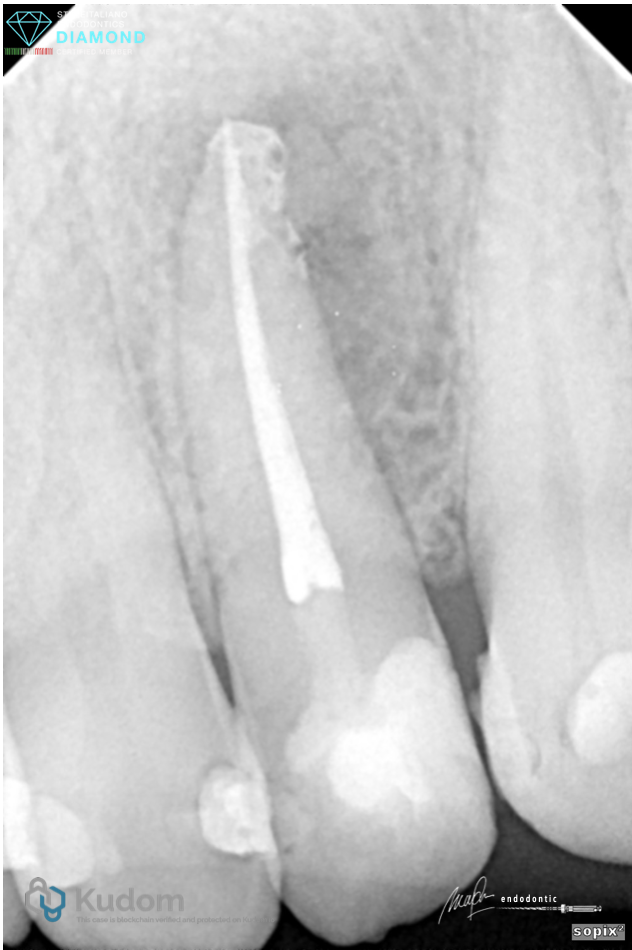

Fig. 2

Tooth was opened, shaped up to working length unit final size of 30/.05. NaOCl 6% was used in between instruments. Activation of irrigants was 6% of NaOCl with EDDY tip for 6 cycles, each are 30 seconds. Final irrigation was 17% EDTA for 1 min.